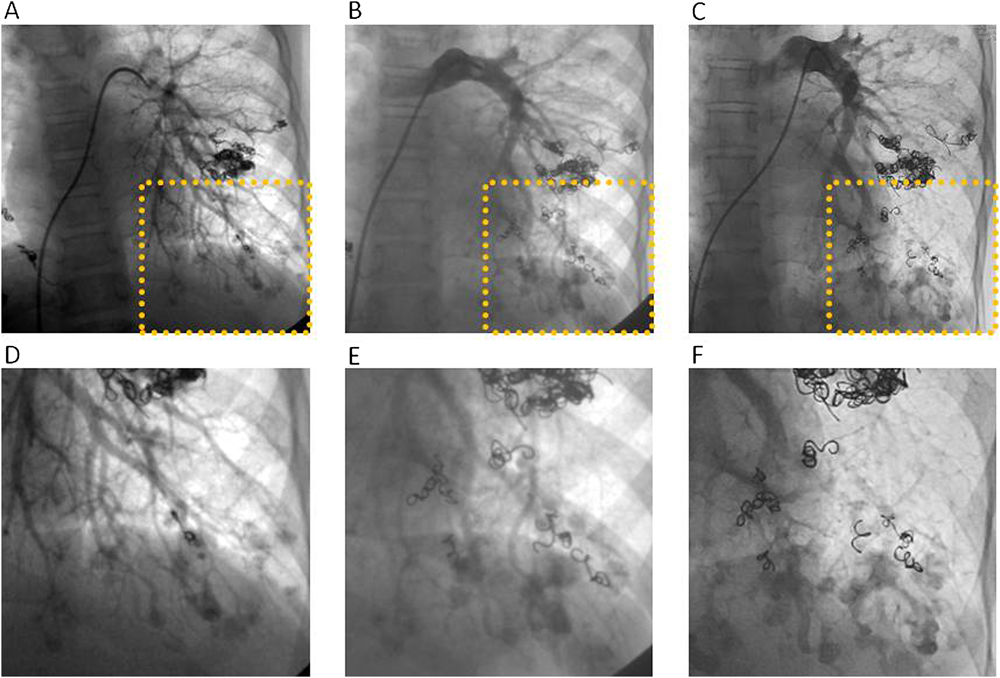

正常肺組織を犠牲にすることを前提としてコイル塞栓術を施行した両側肺全区域びまん性肺動静脈瘻の1例A Case of Diffuse Pulmonary Arteriovenous Malformationss Successfully Treated by Percutaneous Transcatheter Embolization with Sacrifice of Normal Pulmonary Arteries